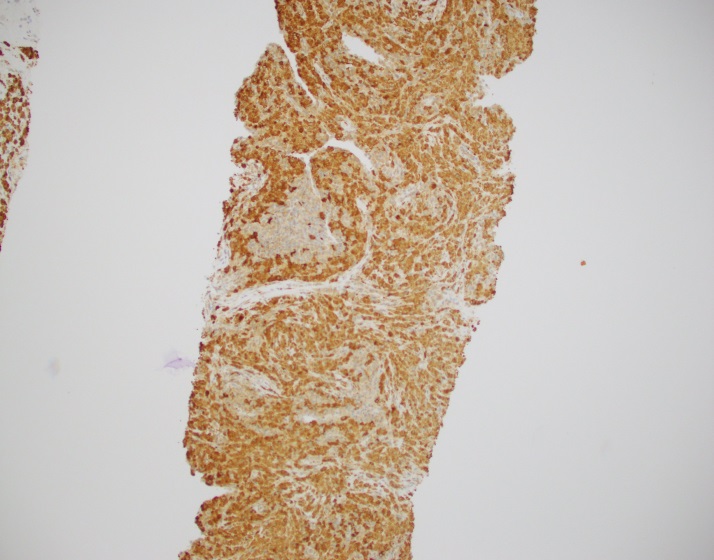

Abdominal ultrasonography demonstrated hepatosplenomegaly with enlarged porta-hepatis lymph nodes. Additionally, chest CT scanning demonstrated bilateral mass-like consolidations, prominent hilar lymphadenopathy, and osteolytic lesions of the vertebral bodies. A comprehensive investigation for opportunistic infections was negative. Lung and vertebral body biopsies (not pictured here) revealed poorly formed granulomas. A blood transfusion was considered; however, the patient had previously been demonstrated to express anti-Kx antibodies, which would require transfusion with exceedingly rare blood products.

The McLeod phenotype is frequently associated with CGD due to the proximity of the XK gene to the CYBB gene on the X chromosome. The CYBB gene encodes for a subunit of the NADPH oxidase enzyme complex. A deficiency in NADPH oxidase activity leads to the characteristic increased susceptibility to severe bacterial and fungal infections seen in CGD. The nitroblue-tetrazolium test can be used to evaluate NADPH oxidase activity in the white blood cells and can help make a diagnosis of CGD. Histologically, CGD can show prominent necrotizing and non-necrotizing granulomas in various locations throughout the body.